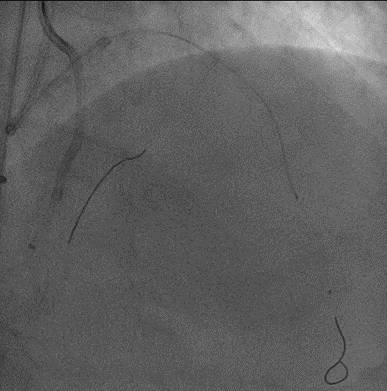

手术影像

LAD、LCX双支 CTO ,LAD 近端50%狭窄

RCA粗大,支架代偿良好。远端60%狭窄,PDA开口80%狭窄

策略讨论:双支CTO,闭塞段残端清晰,钙化,右冠造影可见PLV/PDA侧供LCA。由于有前降支PCI失败史,该次已经做好充分准备,大概率需要逆向PCI。